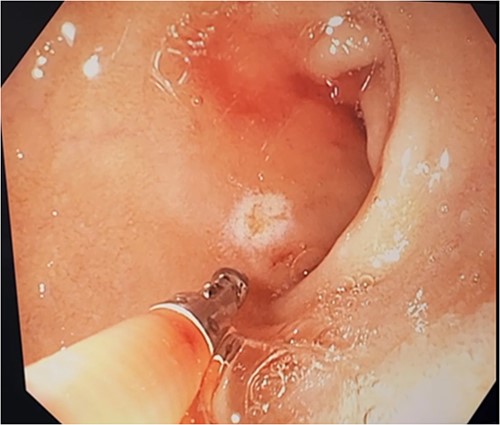

An 85-year-old female presented to hospital with melena and anaemia. She was functionally independent. Her past medical history included hypertension, and medications included irbesartan and low dose aspirin for primary cardiovascular prevention. She was haemodynamically stable with a haemoglobin of 75 g/L (previously normal) and urea of 21.9 mmol/L. CT-angiogram (CT-A) demonstrated no active contrast extravasation. She received two units of packed red blood cells (PRBCs), was commenced on intravenous pantoprazole, and underwent gastroscopy. This revealed a linear ulcer on the greater curvature of the stomach 5 cm from the gastroesophageal junction (GOJ) with an adherent clot and no active bleeding (Figs 1 and 2). The ulcer was injected with adrenaline and haemostasis achieved. The first and second part of the duodenum (D1, D2 respectively) appeared normal.

Initial gastroscopy - linear gastric ulcer on greater curvature of stomach.